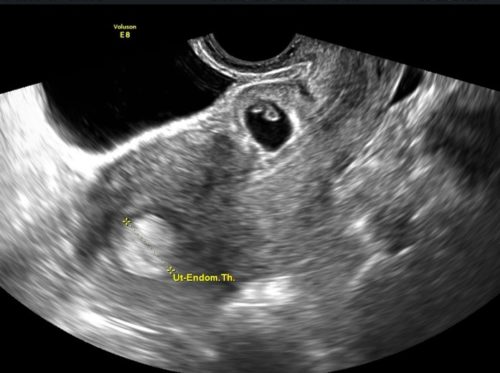

University of Utah Study Finds Surgical Management Superior for Cesarean Scar Ectopic Pregnancies